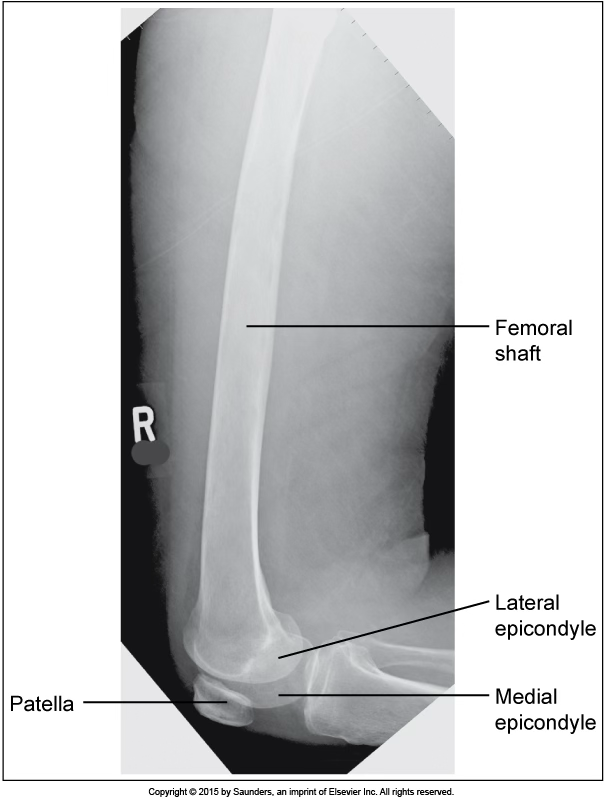

lateral femur

accurate positioning